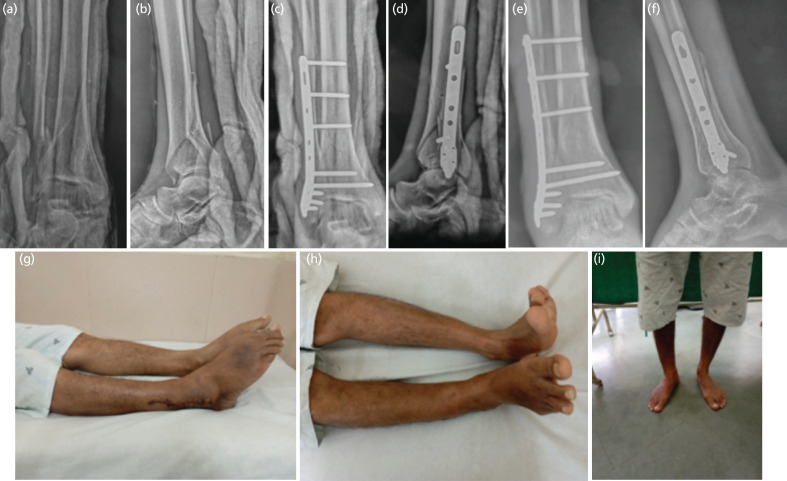

Introduction: Despite recent advances, management of distal tibial fractures is challenging, with high rate of complications. Fibula pro tibia plating technique fixes fibula and tibia together, via laterally placed fibular plate without disturbing the tibial soft tissue sleeve. We contemplated this pilot study to assess effectiveness of fibula pro tibia plating in management of distal tibia fibula fractures.

Materials and methods: A total of 30 patients with distal tibia fibula fractures with fracture line extending within 5cm from tibial plafond were managed with fibula pro tibia plating, with or without minimal articular fixation. Outcome evaluation was done by union, union time, alignment and functional outcome as assessed by AOFAS score.

Results: Mean age in the series was 39.4 years with male to female ratio of 3:2. Mean duration of surgery, blood loss and C arm exposure were 79 minutes (range 52 to 98min), 80ml (range 62 to 102ml) and 48 shoots (range 36 to 81 shoots), respectively. All fractures united in mean union time of 10.2 weeks (range 9 to 14 weeks) with acceptable alignment in all the patients except one. Mean AOFAS score was 86.3 (range 70 to 93) with 29 patients having good to excellent outcome. One patient had varus malunion and in one case infection was seen.

Conclusion: Fibula pro tibia plating can be successfully used to manage complex distal tibia fractures which leaves the soft tissue and periosteal sleeve undisturbed, thus avoiding wound related problems and leading to early union.